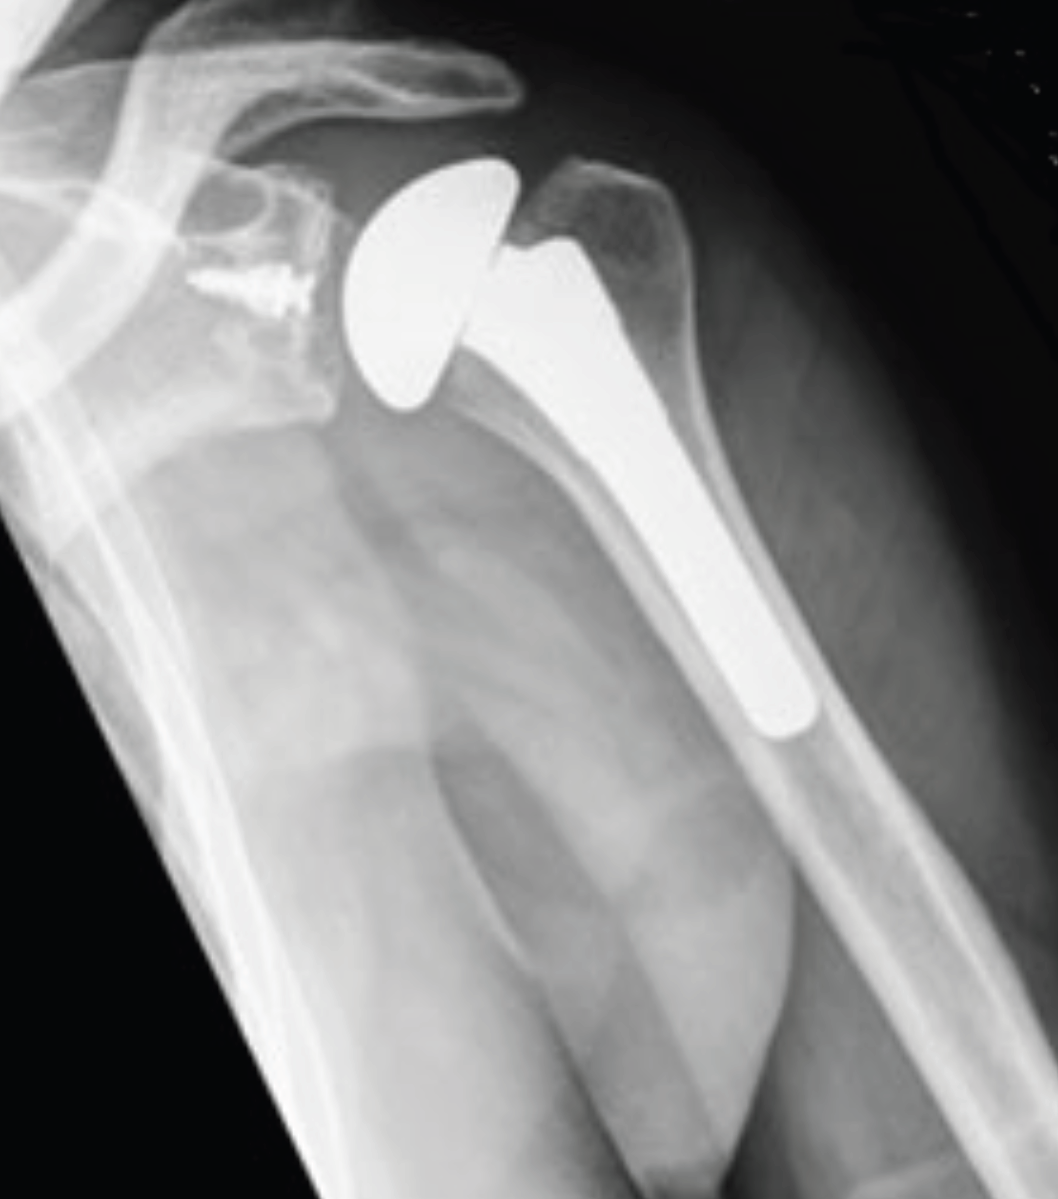

Kısmi Omuz Protezi: Yuvanın (glenoid) sağlam olduğu kol kemiğinin başı veya yumuşak dokunun hasarlı olduğu durumlarda yapılır. Yani bu protez tipinde omuz ekleminin yarısı değiştirilir. Glenoid denilen eklem yuvasına protez parçası yerleştirilmez. Kısmi omuz protezi daha çok parçalı humerus üst uç kırıklarının tedavisinde tercih edilir. Ayrıca glenoidde ciddi şekilde kemik zayıflığı olanlarda ve ciddi derecede yırtık rotator manşet tendonları ve artriti olan bazı omuzlarda kısmi omuz protezi ameliyatı yapılır.

Kısmi omuz protezi. Burada humerus başı total olarak değiştirilir.